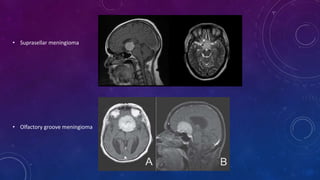

• Suprasellar meningioma •Olfactory groove meningioma

• Suprasellar meningioma

• Olfactory groove meningioma